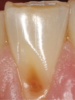

Another intrinsic factor is the patient's gastric acid entering the oral cavity. The source of intrinsic stomach acid may range from rumination or gastroesophageal reflux to chronic alcoholism, pregnancy, or vomiting caused by anorexia nervosa or bulimia nervosa.13 Figure 1 through Figure 3 show the radiographic presentation and clinical examples of dental erosion in advanced stages in the same patient caused by the combination of bulimia nervosa and chronic alcoholism.

Fig 1. Radiographic image of maxillary incisors presenting signicant radiolucency representative of enamel and dentin loss.

Figure 1